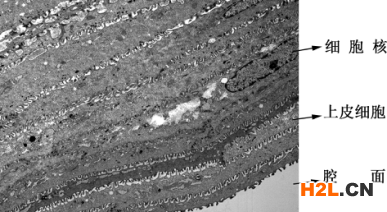

圖1為正常表皮組織透射電鏡圖片,可見條帶狀的復(fù)層鱗狀上皮細(xì)胞整齊排列。圖2為感染后的表皮組織,多種細(xì)菌分布在細(xì)胞周或細(xì)胞質(zhì)基質(zhì)內(nèi),上皮細(xì)胞脫落、壞死。

圖1 正常表皮組織低倍TEM像, 示上皮細(xì)胞的細(xì)胞器及連接結(jié)構(gòu)。